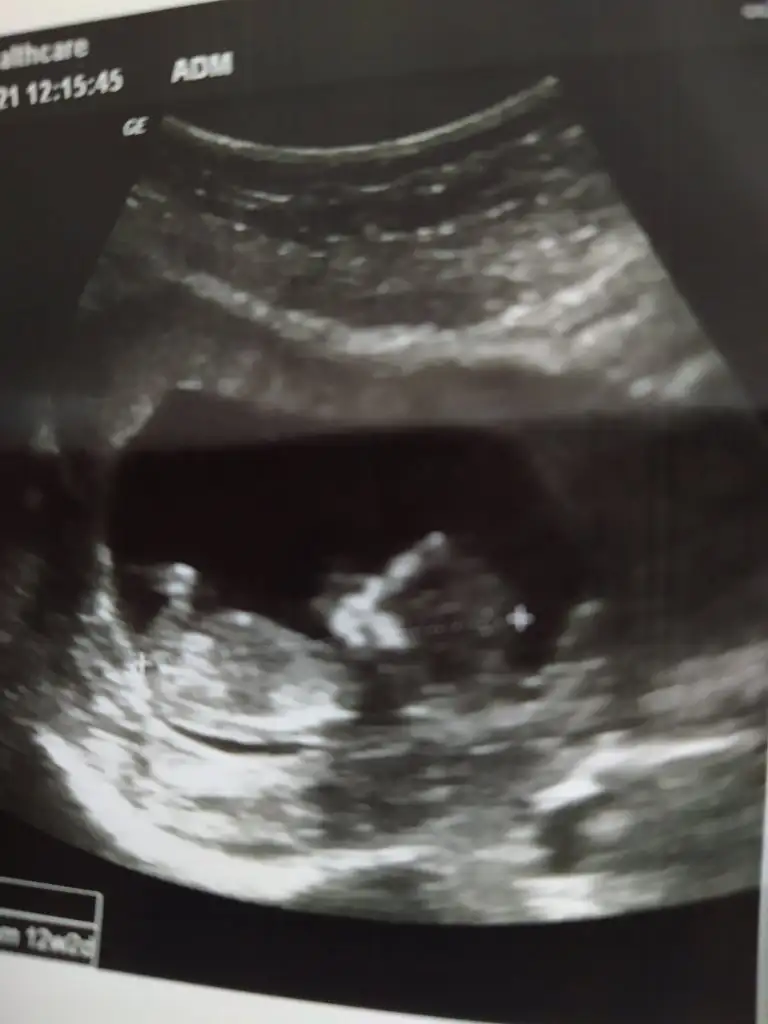

Nubu görünmüyor tipi kız gibi sankiBana da yorum yapabilir misiniz 12 haftada gitmiştim şimdi tekrar gittigimde 18 olucaz ekim sonu merak da var